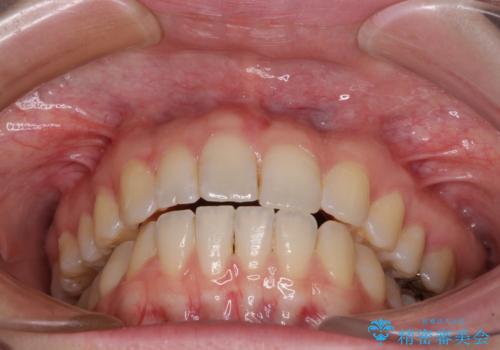

気になる上の歯を改善 インビザライン矯正

- 矯正治療の後戻りが気になるとのことで来院された患者様です。

上顎の後戻りをインビザライン・ライトで治療することとしました。

上顎のみの治療を希望されたため、咬み合わせをしっかりと改善することはできませんでしたが、審美面が大きく改善され、日常生活の機能面でも不具合を感じることはなく、大変満足していただきました。